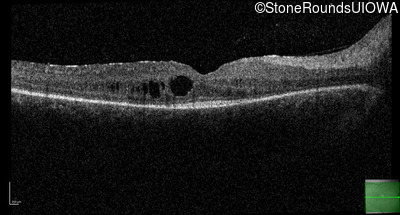

Optical Coherence Tomography - Left - 20/50 -3

Exemplar / OCT Stack